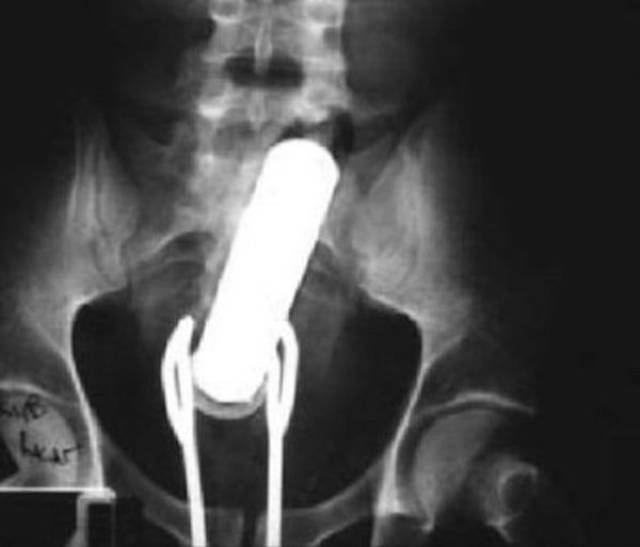

A man with a sexy toy stuck up his ass tried to remove it with salad tongs.

They also got stuck.